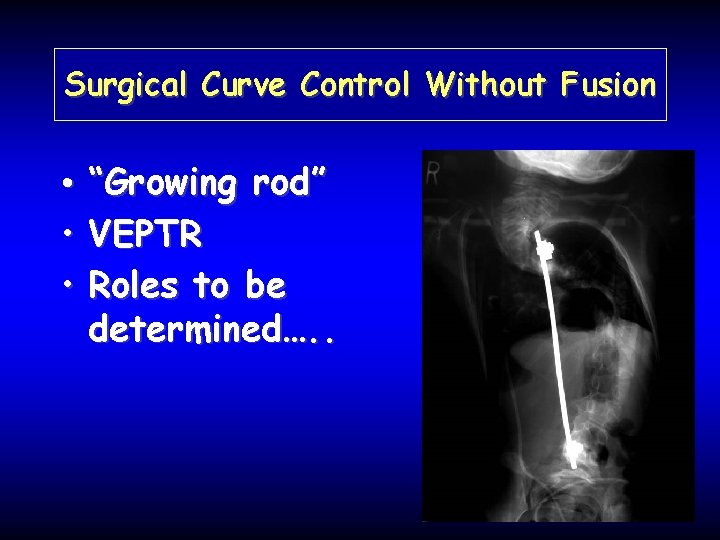

Surgical Curve Control Without Fusion • “Growing rod” • VEPTR • Roles to be determined…. .